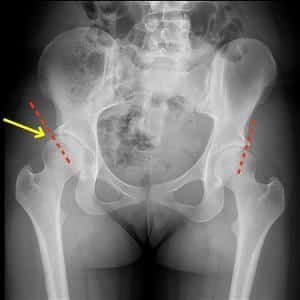

Прогрессирование этого заболевания сопровождается образованием остеофитов и сращиванием вертлужной впадины с головкой бедренной кости, что, в свою очередь, приводит к сужению суставной щели и потере функциональности сустава.

Существует 3 степени остеоартроза вертлужной впадины и головки бедра, которые характеризуются постепенным разрушением сустава. Рассмотрим их особенности подробнее.

На 1 стадии коксартроза наблюдается незначительное разрушение хряща, суставная щель сужена лишь немного.

На 2 стадии разрушение хрящевой ткани значительно усиливается, появляются первые признаки заболевания: боль и скованность.

На 3 стадии наблюдаются более серьезные повреждения тазобедренного сустава. Для этой стадии характерно глубокое разрушение хряща, деформация костей и боль в состоянии покоя. Заболевание приводит к полному разрушению хряща и деформации бедренной кости.

Диагностика заболевания позволяет определить степень повреждения хрящевой ткани и возможность лечения артроза тазобедренного сустава.

Для установления диагноза врач проводит внешний осмотр, анализирует подвижность тазобедренного сустава, а также оценивает изменения в походке и длине ног. Для подтверждения диагноза первичного коксартроза назначаются рентгенография, компьютерная томография и магнитно-резонансная томография. Если пациенту требуется операция, дополнительно берутся анализы мочи, кала, крови и суставной жидкости.